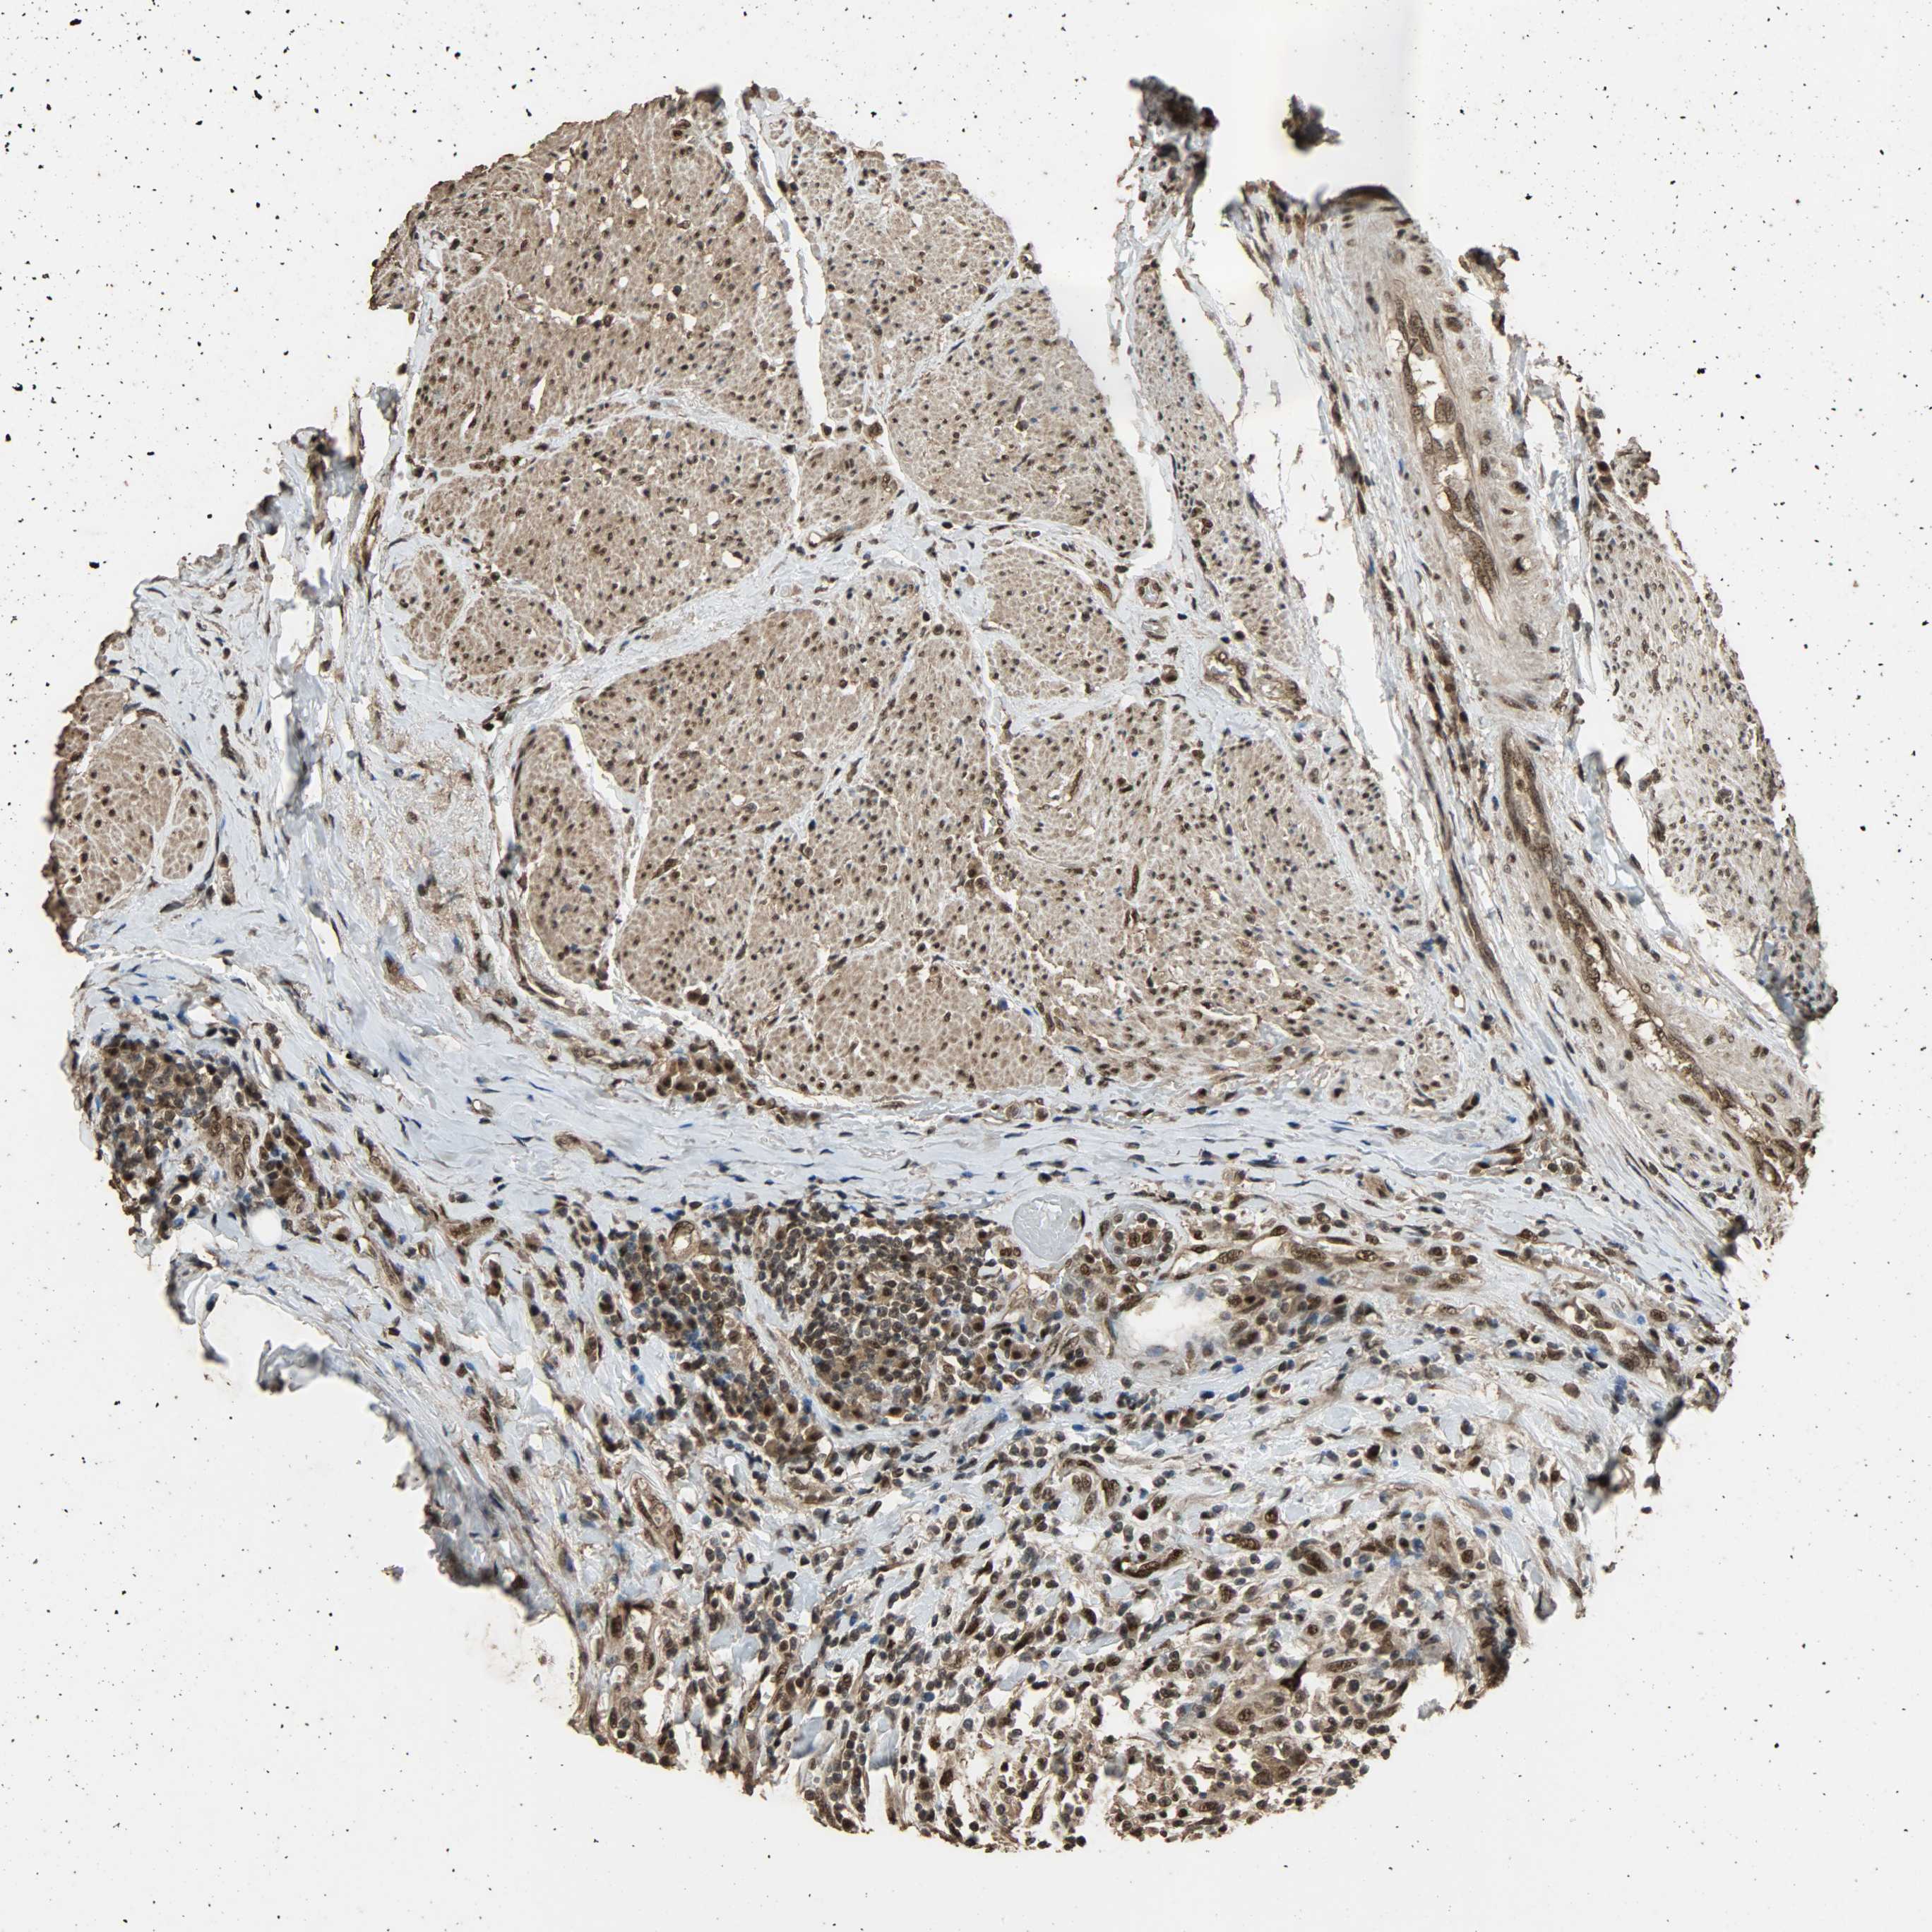

UROTHELIAL CANCER - Protein expressioni

A mouse-over function shows sample information and annotation data. Click on an image to view it in a full screen mode. Samples can be filtered based on level of antibody staining by selecting one or several of the following categories: high, medium, low and not detected. The assay and annotation is described here.

Note that samples used for immunohistochemistry by the Human Protein Atlas do not correspond to samples in the TCGA dataset.

Antibody stainingi

Antibody staining in the annotated cell types in the current human tissue is reported as not detected, low, medium, or high, based on conventional immunohistochemistry profiling in selected tissues. This score is based on the combination of the staining intensity and fraction of stained cells.

Each image is clickable and will lead to virtual microscopy that enables deeper exploration of all samples and also displays staining intensity scores, fraction scores and subcellular localization as well as patient and tissue information for each sample.

Antibody HPA005559

Staining

High

Medium

Low

Not detected

Intensity

Strong

Moderate

Weak

Negative

Quantity

>75%

75%-25%

<25%

None

Location

Nuclear

Cytoplasmic/membranous

Cytoplasmic/membranous,nuclear

Urothelial carcinoma, High grade

Urothelial carcinoma, Low grade